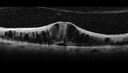

72 year old man 1 month following Avastin injection for recurrent CME with CRVO for 6 months - Vision is 20/200 and OCT shows disorganized retinal inner lasyers

Disorganized Retinal Inner Layers (DRIL)vista 554 veces72 year old man treated with Avastin for CRVO VA is still 20/200 with absent macular edema (Only 1 month post rx)00000